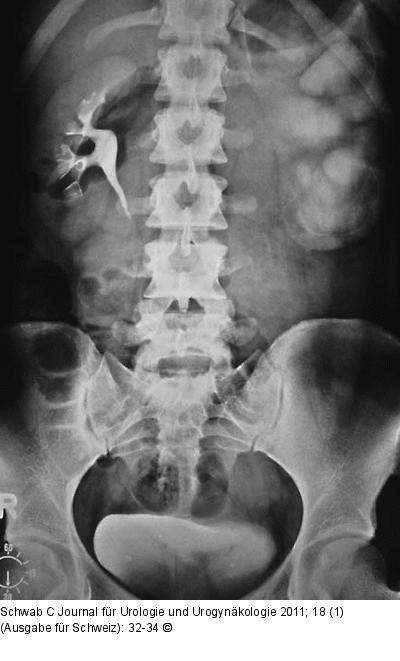

Abbildung 1: Harntrakt - Tumor Harntransportstörung links im IVU bei pyeloureteraler Abgangsstenose. |

Harntransportstörung links im IVU bei pyeloureteraler Abgangsstenose. |